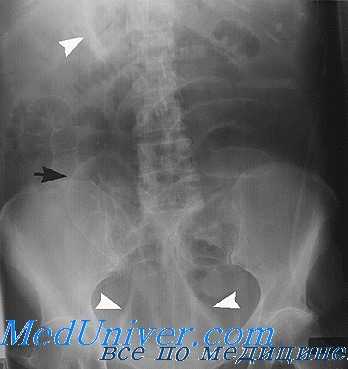

На обзорном снимке или на флюоресцирующем экране брюшная полость отображается в виде более или менее однородной средней интенсивности теневой картиной на фоне скелета данной области. Это объясняется тем, что органы брюшной полости: печень, селезенка, желудок, кишечник и т. д. имеют одинаковую плотность и рентгенологически не дифференцируются раздельно друг от друга. Но нередко на обзорном снимке бывает видна верхняя часть желудка (так как в ней содержится воздух) — в виде так называемого желудочного пузыря. Иногда бывают видны небольшие скопления газа в петлях тонкого и особенно толстого кишечника — в печеночном и селезеночном изгибах. Прямая кишка часто содержит газ и твердые каловые массы и легко поэтому иногда распознается по своей форме и положению.